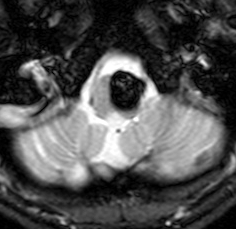

脳幹部の海綿状血管腫 brainstem cavernous hemangioma

2度の延髄内出血を生じた海綿状血管腫です。でも初回の出血からすでに27年間がたちます。症状も回復して麻痺もなくていまは社会生活に困ることはありません。脳幹部の海綿状血管腫の中には1ヶ月に何回もひどい出血を繰り返すのもあるのですが,この例のように30年近い間に軽い出血が2回だけというのもあります。残念ながら正確にこれを予測することはできません。この患者さんの海綿状血管腫は手術で摘出すれば麻痺などの合併症の可能性があるのでしません。